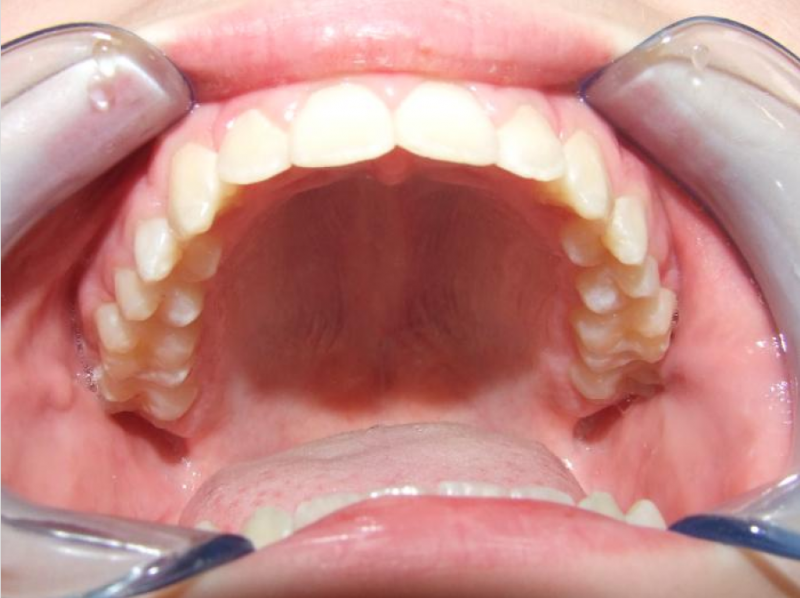

Leeftijd bij aanvang: 10 jaar

Bonded Hyrax + volledig vast onderkaak

Volledig vast bovenkaak + expander

Wrap + c-c bar onderkaak

Leeftijd bij afname: 12 jaar

Voor behandeling

Na behandeling